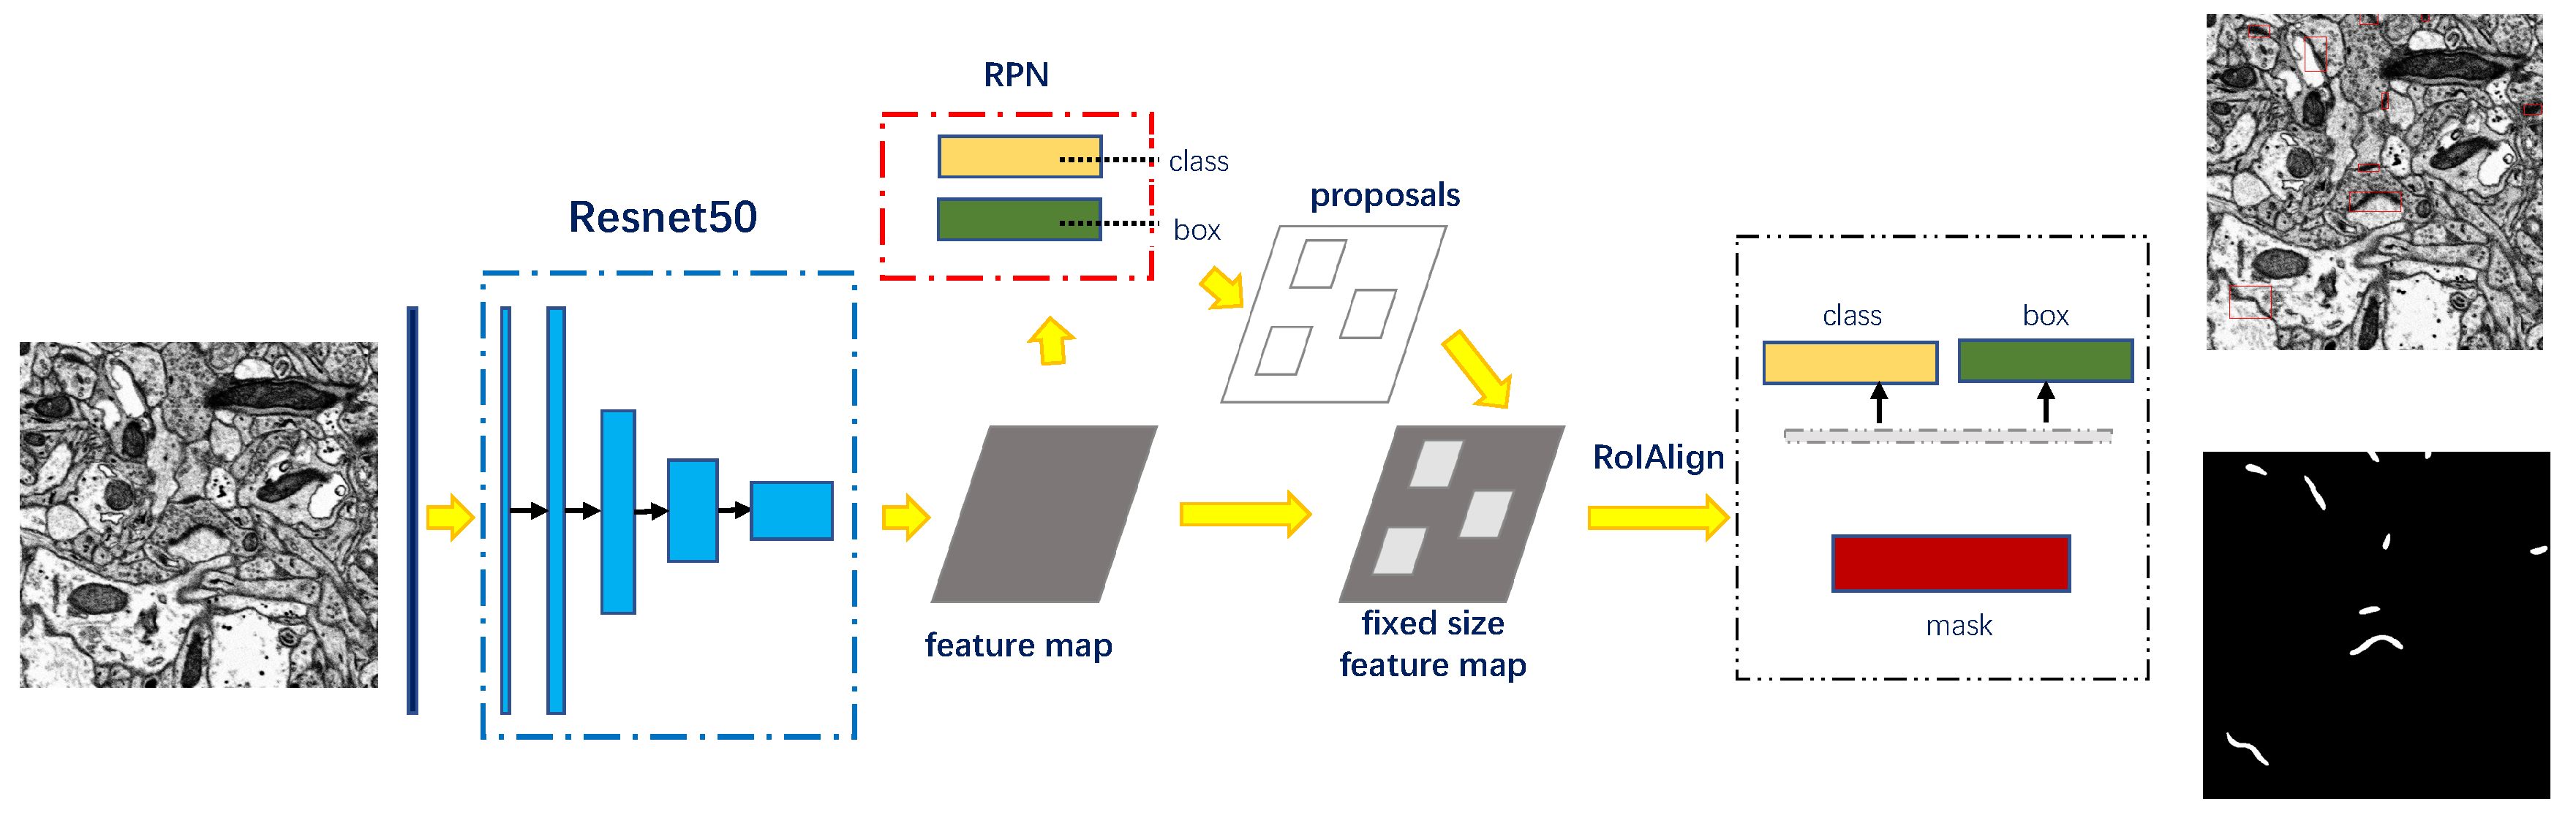

3.2. Recognition of Synapse

3.2.1. Detection and Segmentation with Mask R-CNN